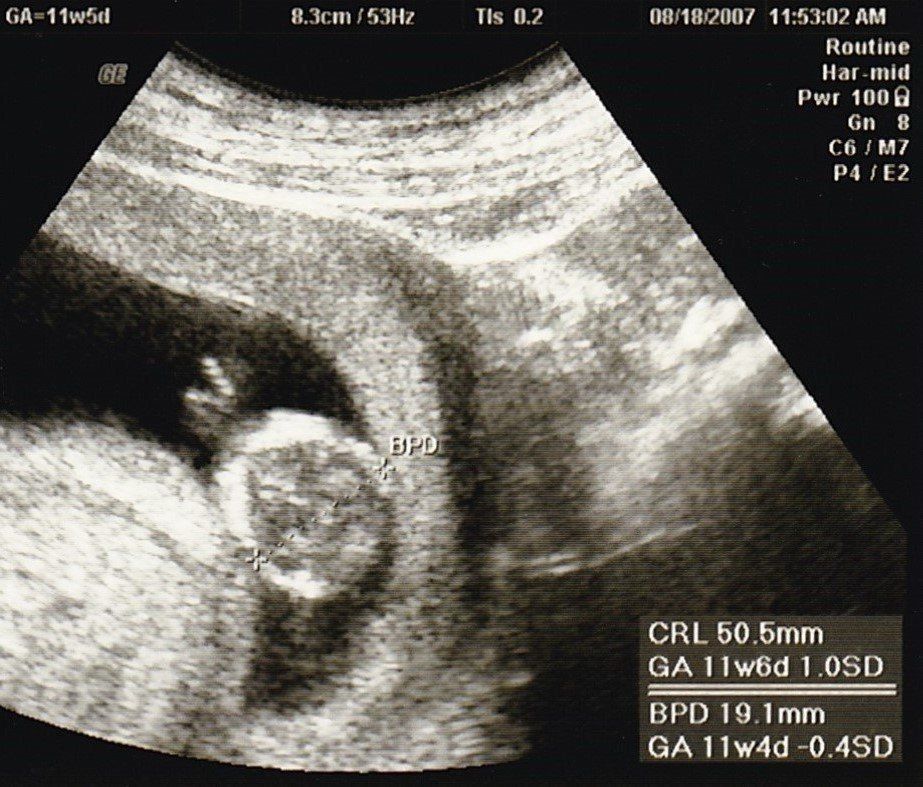

妊娠11週目のエコー写真

産院では、動画で赤ちゃんが動く映像を見せてくれて、検診に行くのが楽しみでした。

この頃、胎児染色体検査(ダウン症かどうかの検査)をするかを決めたり、“ソフロロジー法”の資料を読んだりすることで、私はどういう出産をしたいかを考えるようになりました。(胎児染色体検査はその結果によって産むか産まないかを考えることをしたくなかったので、受けるのをやめました。)